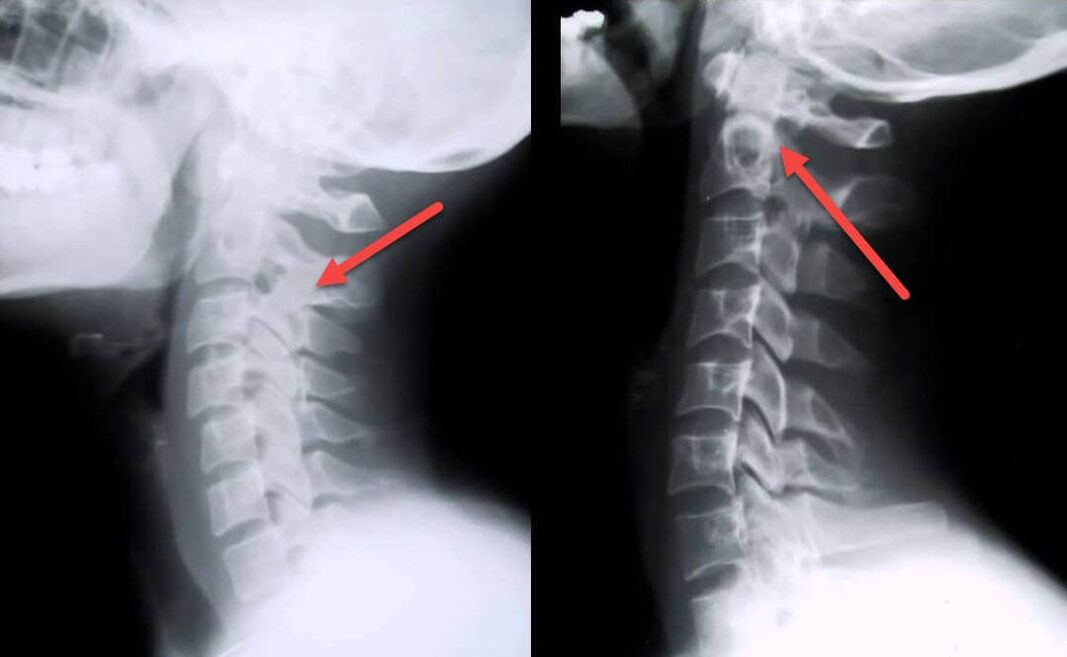

O procedemento diagnóstico máis informativo é a radiografía. As patoloxías de 1o grao corresponden a 1a ou 2a etapa radiolóxica. As imaxes resultantes visualizan os signos típicos da enfermidade.

| Etapas de raios X da osteocondrose cervical de 1º grao | Sinais característicos |

|---|---|

| Etapa 1 | Cambios menores na curvatura da columna vertebral na rexión cervical, que afectan a un ou máis segmentos |

| Etapa 2 | Lixeiro engrosamento dos discos intervertebrais, deformación dos procesos uncinados, endereitamento da lordose, pequenos crecementos das estruturas óseas |